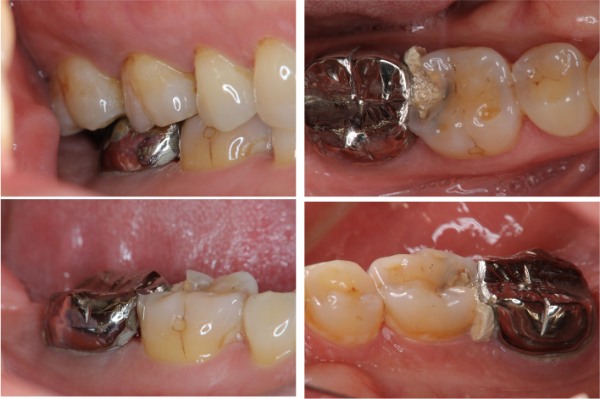

治療前,二次蛀牙,咬頭受損

蛀牙未到牙髓

冠塊體體製備